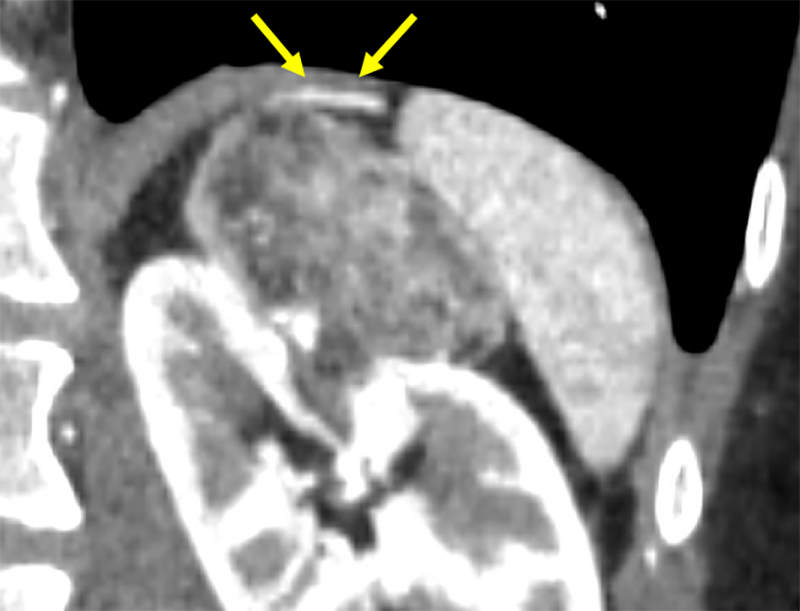

本症例では術前の造影CTから左腎動脈上極枝のほか、左腎動脈本幹から分岐する左上腎被膜動脈が栄養血管として同定され、この画像情報を参考にして塞栓術が施行された。術中の血管造影においても左上腎被膜動脈が腫瘍を栄養する血管として確認され、術前の造影CT所見の通りであった。

この早期動脈相は術前の腎動脈解剖を詳細に把握するために最も重要な撮影時相である。薄層スライス厚での撮影により、高精細なMPR(多断面再構成)、MIP(最大値投影法)による3D画像処理が可能となり、腎動脈の起始部から末梢分枝まで、さらに異所性分岐などの解剖学的バリエーションも明瞭に描出できる。特に塞栓術においては、標的血管の同定と周囲血管との関係性の把握が重要であり、これらの三次元的な血管構築の評価は手技の成功に直結する。このようにbolus tracking法を用いた精密なタイミング制御と高分解能撮影の組み合わせにより、塞栓術の安全かつ確実な施行に必要な血管解剖情報を包括的に取得している。